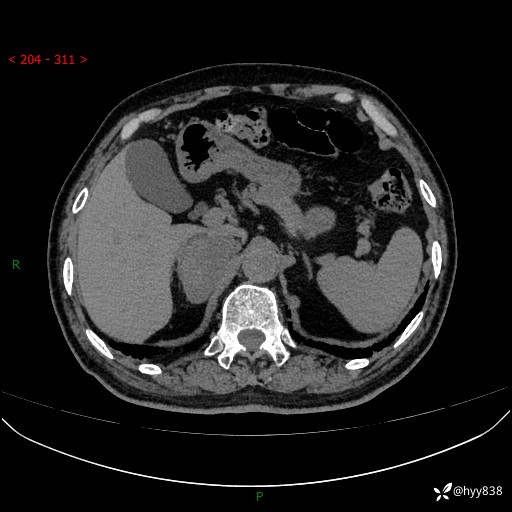

【患者信息】:76岁/男

【主诉】:检查发现右侧肾上腺占位6天

【现病史及既往史】:患者6天前体检发现右侧肾上腺占位,无腰痛,无放射痛,无尿频、尿急、尿痛及肉眼血尿,无畏寒、发热,无恶心、呕吐,今为求进一步治疗,遂来我院就诊,门诊拟“右侧肾上腺占位”收住入院。 起病以来,患者精神、饮食、睡眠可,大小便如常,体力体重无明显变化。

【检查】:肾上腺CT平扫+增强